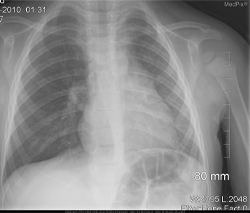

• En la radiografía de tórax no se encuentran signos de consolidación o infiltrados, leve hiperinsuflación pulmonar derecha